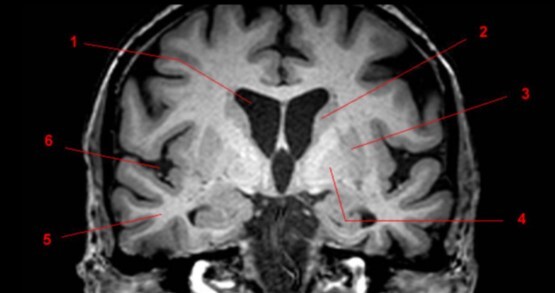

6

Q

Label 1-4

A

1. Lentiform nucleus

2. Caudate nucleus

3. Lateral ventricle

4. Cerebellum

7

1. Head of Caudate nucleus

2. Lateral ventricle

3. Thalamus